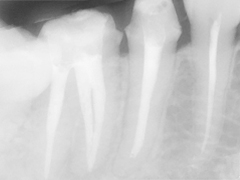

根管治療では清掃した根管内に再び細菌が侵入、繁殖しにくいよう根管充填材により根管内を塞ぎます。このレントゲンでは根尖(根の先)まで充填材が詰まっていないことがわかります。つまり充填材が入っていない根の中の空間で細菌が繁殖し化膿しやすい環境となっているのです。一般的な根管治療では手探りの治療であるため、このような不完全な治療がとても多く認められ、痛みや抜歯の原因となっています。

レントゲンで見ても金属以外の異物が根の中から取り除かれたことが分かります。

術前

根管内を徹底的に清掃し最後に根管内を充填材により密封します。

根の先まで治療が行き届いていることがわかります。